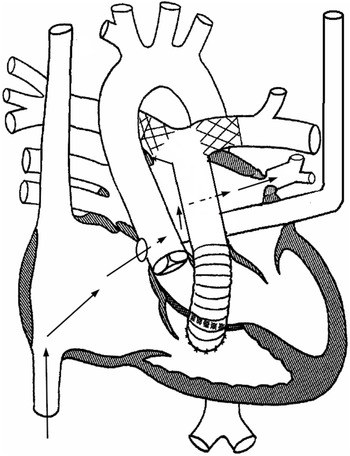

Figure 2. Schematic diagram explaining the anatomy. Black arrows depict the course that was utilised to access the stenotic pulmonary vein. The catheters were advanced from the right atrium coronary sinus ostium unroofed coronary sinus left atrium left upper pulmonary vein.

A 3-month-old male weighing 4.8 kg was born with truncus arteriosus, interrupted aortic arch, and persistent left superior caval vein draining into the right atrium via what was initially thought to be fully roofed coronary sinus. He underwent surgical repair on day 10 of life consisting of end-end arch repair, ventricle septal defect closure, and placement of right ventricle-pulmonary artery homograft. Immediately after repair, stents were placed in the proximal right and left pulmonary arteries due to severe stenosis. Due to the persistent low oxygen saturation (in the mid-80s), a bubble study echocardiogram was performed which revealed that the coronary sinus was partially unroofed. A cardiac CT scan 3 weeks post-repair showed stenosis of the left pulmonary artery proximal to the stent, as well as normal size common right and common left pulmonary veins. An echocardiogram at 3 months of age revealed increased estimated right ventricle systolic pressure, increased flow velocity in the branch pulmonary arteries, flow turbulence in the common left pulmonary vein, no atrial septal defect, dilated coronary sinus ostium, and unroofed distal coronary sinus with the unroofed segment measuring 7 mm in length (Figs 1 and 2). He was taken to the cardiac catheterisation lab for possible intervention on the stented pulmonary arteries. The right femoral vein and artery were accessed using a 5-Fr sheath and a 20-gauge catheter, respectively. Haemodynamic measurements showed elevated distal pulmonary artery pressure with a mean of 26 mmHg and an elevated calculated pulmonary vascular resistance (9.8 Wood units × m2). Balloon angioplasty was then performed in the right and left pulmonary artery stents, along with the placement of an additional stent in the proximal left pulmonary artery to treat the aforementioned stenosis. The left pulmonary artery wedge angiogram showed severe ostial stenosis of the common left pulmonary vein (Fig 3A). Attempts to cross the atrial septum (probing the foramen ovale) were unsuccessful. Knowing the patient had an unroofed coronary sinus, we elected to attempt left atrial access via the coronary sinus. A coaxial system consisting of a 5-Fr JR4 guide catheter (Medtronic), 4-Fr JR 2 catheter (Cook Medical), and 0.035" angled glide wire (Terumo) was inserted through the right femoral vein sheath into the coronary sinus. The catheters were oriented superiorly and rightward. The wire was advanced to cross the coronary sinus into the left atrium. The catheters were then advanced over the wire inside the left atrium. The angled glide wire was exchanged for a 0.014" Choice wire (Boston Scientific). The catheters were turned toward the common left pulmonary vein. The Choice wire was manipulated to cannulate the common left pulmonary vein. The JR2 catheter was then advanced over the wire into the left lower pulmonary vein (Fig 2). Pressure measurements revealed a gradient of 16 mmHg across the stenosis. Angiograms showed severe stenosis of the left pulmonary vein just distal to the ostium and the normal pulmonary vein measuring 4.2 mm (Fig 3B). The Choice wire was exchanged for a stiffer coronary wire [0.014" Asahi Grand Slam wire (Abbott)] to provide more support for pulmonary vein stent placement. Then, the 5-Fr guide catheter was advanced over the JR2 catheter inside the vein and the JR2 catheter was removed. A 4 × 8 mm Synergy everolimus-eluting stent (Boston Scientific) was advanced over the wire inside the guide catheter and centred across the stenotic portion. The stent was deployed by inflating the balloon to 18 atmospheres (the rated burst pressure) to achieve a stent diameter slightly larger than 4 mm to match the normal distal pulmonary vein segment. Angiography revealed a well-positioned stent (Fig 3C). Pressure measurement showed no gradient across the stent. No significant improvement in his oxygen saturation was noticed at the end of the procedure. The patient was discharged home on the same home dose of aspirin and started on Sildenafil. Over the next few weeks following the procedure, his oxygen saturation has increased to 93–95%.

Many features make our case unique. The association of pulmonary vein stenosis in patients with truncus arteriosus and unroofed coronary sinus has never been described in the literature. Reference Feins, Ireland and Gauvreau2,Reference Kalfa, Belli and Bacha3 Additionally, the exact mechanism of pulmonary vein stenosis is unknown. However, it falls under the category of primary pulmonary vein stenosis as it affected a vein that has never been operated on. Reference Vanderlaan, Rome, Hirsch, Ivy and Caldarone1 The presentation of pulmonary vein disease was late, as imaging 3 weeks later post-repair showed no pulmonary vein stenosis. Primary pulmonary vein stenosis in patients with associated CHD is usually either identified prior to or immediately after the surgical repair and is usually attributed to the technique of repair. Reference Feins, Ireland and Gauvreau2,Reference Kalfa, Belli and Bacha3 Furthermore, the presence of an unroofed coronary sinus allowed for safe access to the left atrium without the need to create a new atrial septal defect. To our knowledge, this is the first time such an approach has been described.